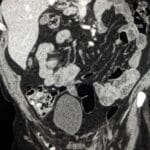

42 yr male with a history of neonatal umbilical vein catheterization presenting with hematemesis and splenomegaly.

Diagnosis: Cavernous transformation of the portal vein

- CT: Nonvisualization of the main portal vein trunk replaced by numerous tortuous periportal collaterals (cavernoma); may appear as a solid tumor-like enhancing hilar mass; associated signs include splenomegaly and gallbladder varices.

- Signs: Portal cavernoma: A sponge-like mass or tangle of enhancing vessels in the porta hepatis representing dilated periportal collaterals.